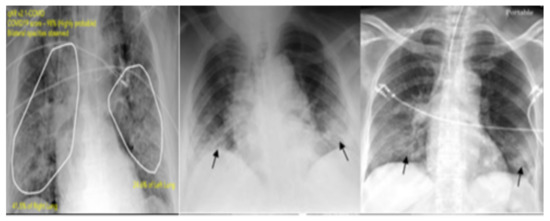

4.1. Feature Extraction Step

4.2. Data Sets